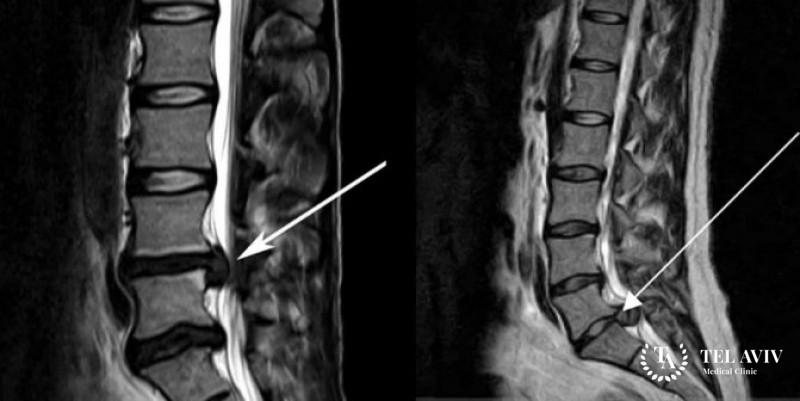

- Магнитно-резонансная томография выявит причину, очаг заболевания, его вид и степень роста, сосудистые изменения.